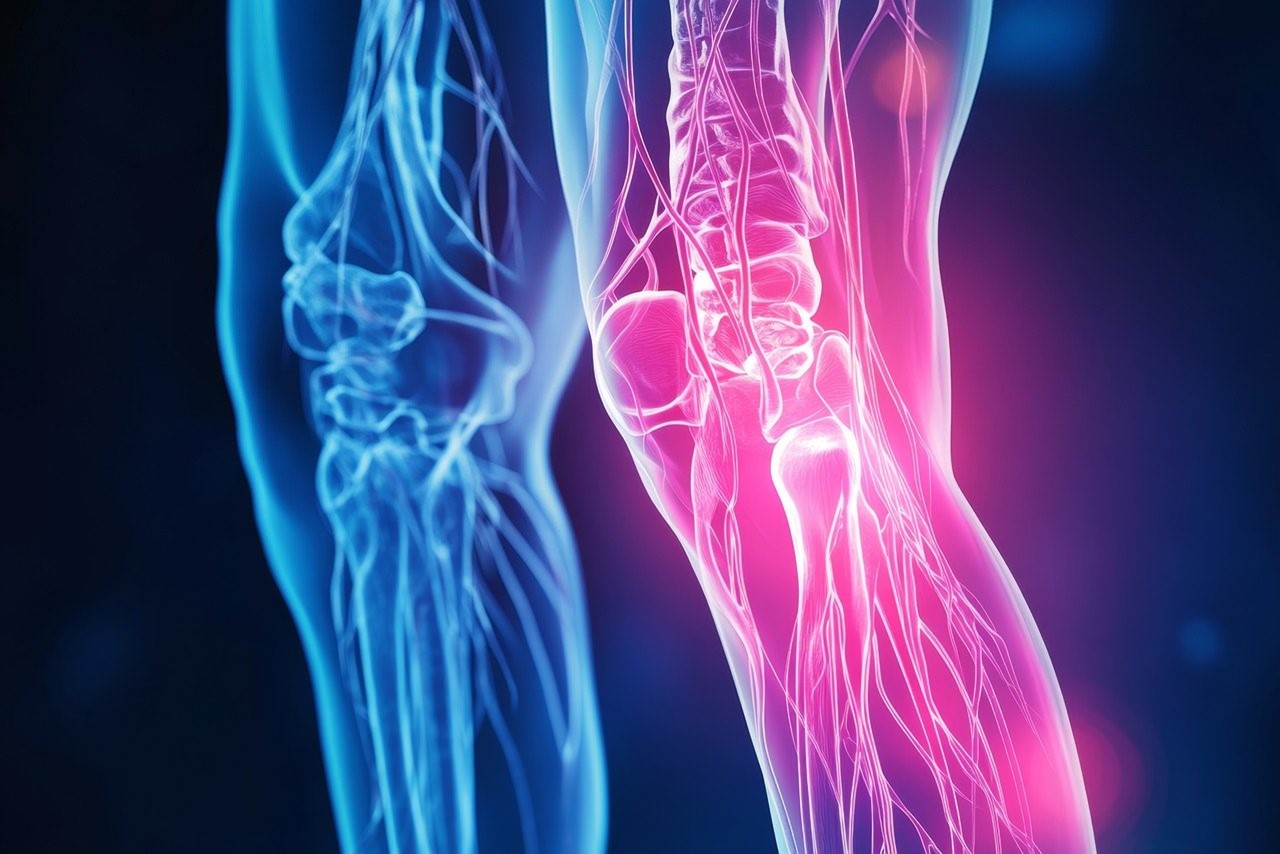

- Η προσπέλαση STAR είναι μία ελληνική χειρουργική καινοτομία με άριστα αποτελέσματα και χρησιμοποιείται σε επεμβάσεις στο ισχίο.

- Οι επιστήμονες υπογραμμίζουν τα πλεονεκτήματα της προσπέλασης STAR, την ελάχιστη καταστροφή και την ταχύτητα επέμβασης, προσφέροντας εξαιρετικά αποτελέσματα στους ασθενείς.

Ο κ. Τσιρίδης ανέφερε ότι η εφαρμογή της προσπέλασης STAR ξεκίνησε πριν επτά χρόνια και ότι δημοσιεύτηκαν τα αποτελέσματα 522 επεμβάσεων που έγιναν τα τελευταία πέντε χρόνια με τη μέθοδο αυτή με εξαιρετικά αποτελέσματα. Η μέθοδος αυτή έχει υιοθετηθεί στη Νέα Υόρκη, παρουσιάστηκε πρόσφατα στην Αυστραλία και τις επόμενες ημέρες θα την παρουσιάσει ο κ. Τσιρίδης στην Ιαπωνία και στην Κίνα.

«Τα πλεονεκτήματα της προσπέλασης STAR είναι η ελάχιστη καταστροφή, η μεγάλη ταχύτητα επέμβασης, η μεγάλη καθαρότητα κατά τη διάρκεια της επέμβασης και τα άριστα αποτελέσματα σε ό,τι αφορά την ικανοποίηση του ασθενούς. Ο ασθενής σηκώνεται την ίδια ημέρα, περπατά, είναι ικανοποιημένος, φεύγει σπίτι του, ενδεχομένως την επομένη και το αποτέλεσμα είναι πολύ καλό. Φυσικά, πάντοτε με προσοχή και φυσικά πάντα με σεβασμό στις ιατρικές ενδείξεις. Τη μέθοδο αυτή την χρησιμοποιούμε και στο Παπαγεωργίου και στο Διαβαλκανικό και εφαρμόζεται παντού από όλους τους εκπαιδευόμενους μου και απ όλους τους ανθρώπους που είναι κοντά μου και πολλούς άλλους» εξήγησε ο κ. Τσιρίδης.